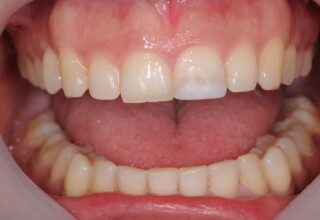

Οι όψεις ρητίνης προσφέρουν έναν οικονομικό τρόπο αισθητικής βελτίωσης της εμφάνισης των προσθίων δοντιών ενίοτε και των προγομφίων. Οι δυνατότητες τους πολλές, μπορούν να κάνουν και θαύματα! Ο μονός περιορισμός η κλινική ευχέρεια και η φαντασία του επεμβαίνοντος. Σε αυτήν την ασθενή οι τέσσερεις άνω τομείς είχαν ο καθένας το δικό του πρόβλημα(δυσχρωμία, απόκλιση) και επιπλέον: διαστήματα, πολλαπλές αποχρώσεις, κακή σχέση μεταξύ τους και με τα ούλα. Αποκαταστάθηκαν με τέσσερεις άμεσες όψεις ρητίνης (η μια πάνω σε στεφάνη πορσελάνης εμφυτεύματος!!!) οι οποίες κατασκευάστηκαν ενδοστοματικά!